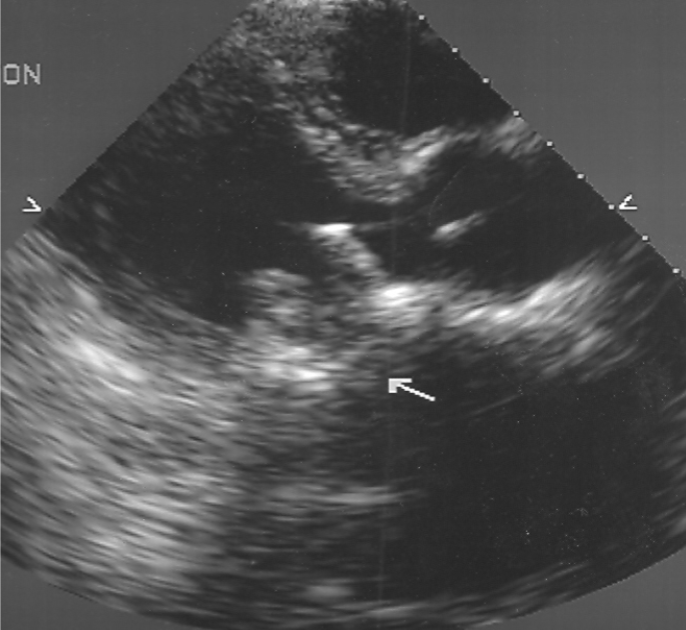

Mechanical Valves 2D findings:

produce shadowing and reverberation

appearance will vary d/t:

angle of insertion by surgeon

type of valve used

TTE can be difficult

take extra time to evaluate and image

TEE Evaluation of Mechanical Valves:

method of choice

assess regurg

may be masked by prosthesis on TEE

assess anatomic detail:

LA appendange

thrombus / vege

ring abscess

pseudoaneurysm

intraoperative monitoring for:

perivalvular leak

regurg

dysfunction